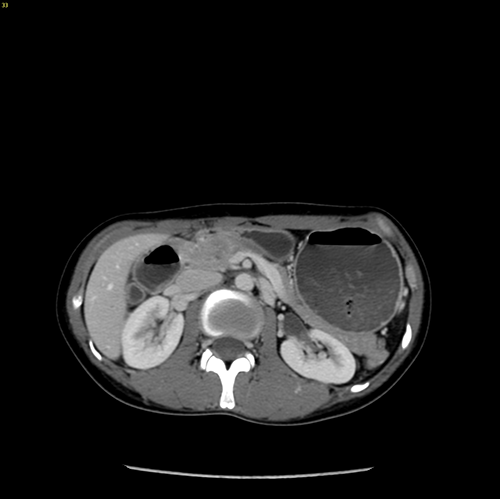

胰腺头颈假性乳头状瘤 -胰腺中段切除